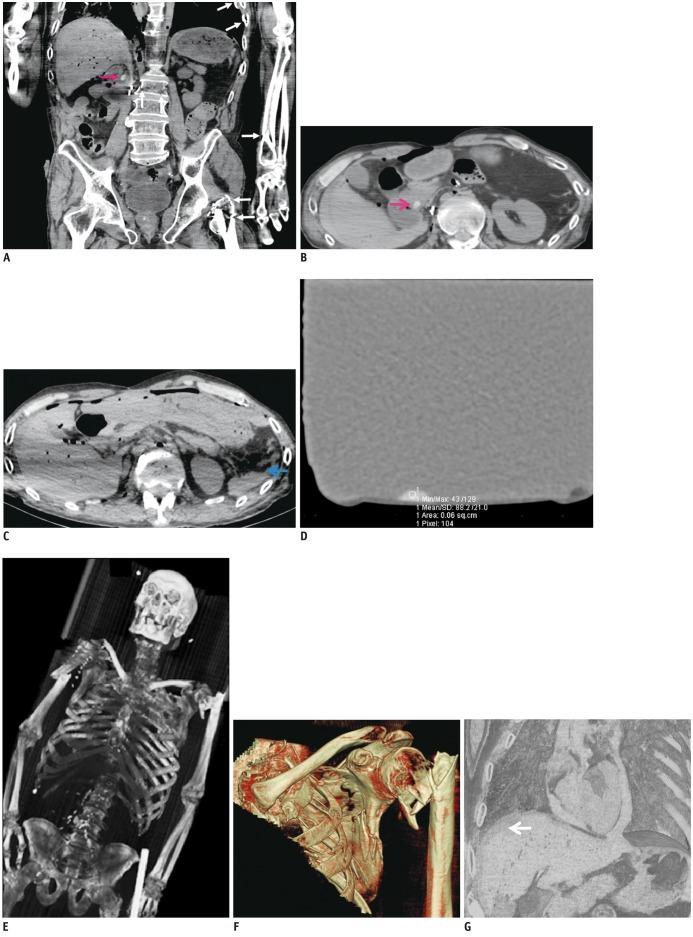

A 63-year-old man was found in the street after overrun by a car. Postmortem CT revealed multiple bone fractures, but surprisingly all without any relevant hemorrhage which would have been expected under such circumstances. A round radiopaque formation was found in the duodenum, which was reminiscent of ingested tablets. The toxicological analysis revealed high concentrations of zopiclone and alcohol. By combining radiologic and forensic results, zopiclone and alcohol intoxication were concluded as the cause of death, followed by a postmortem overrun accident.

一位 63 岁男性被车碾压后倒在街上。尸检 CT 显示多处骨折,但令人惊讶的是,所有骨折均无任何情况下预期的相关出血。在十二指肠中发现一个圆形不透射线的形成物,这让人想起摄入的片剂。毒理学分析显示佐匹克隆和酒精浓度很高。通过结合影像学和法医学结果,佐匹克隆和酒精中毒被认为是死亡原因,随后是死后碾压事故。